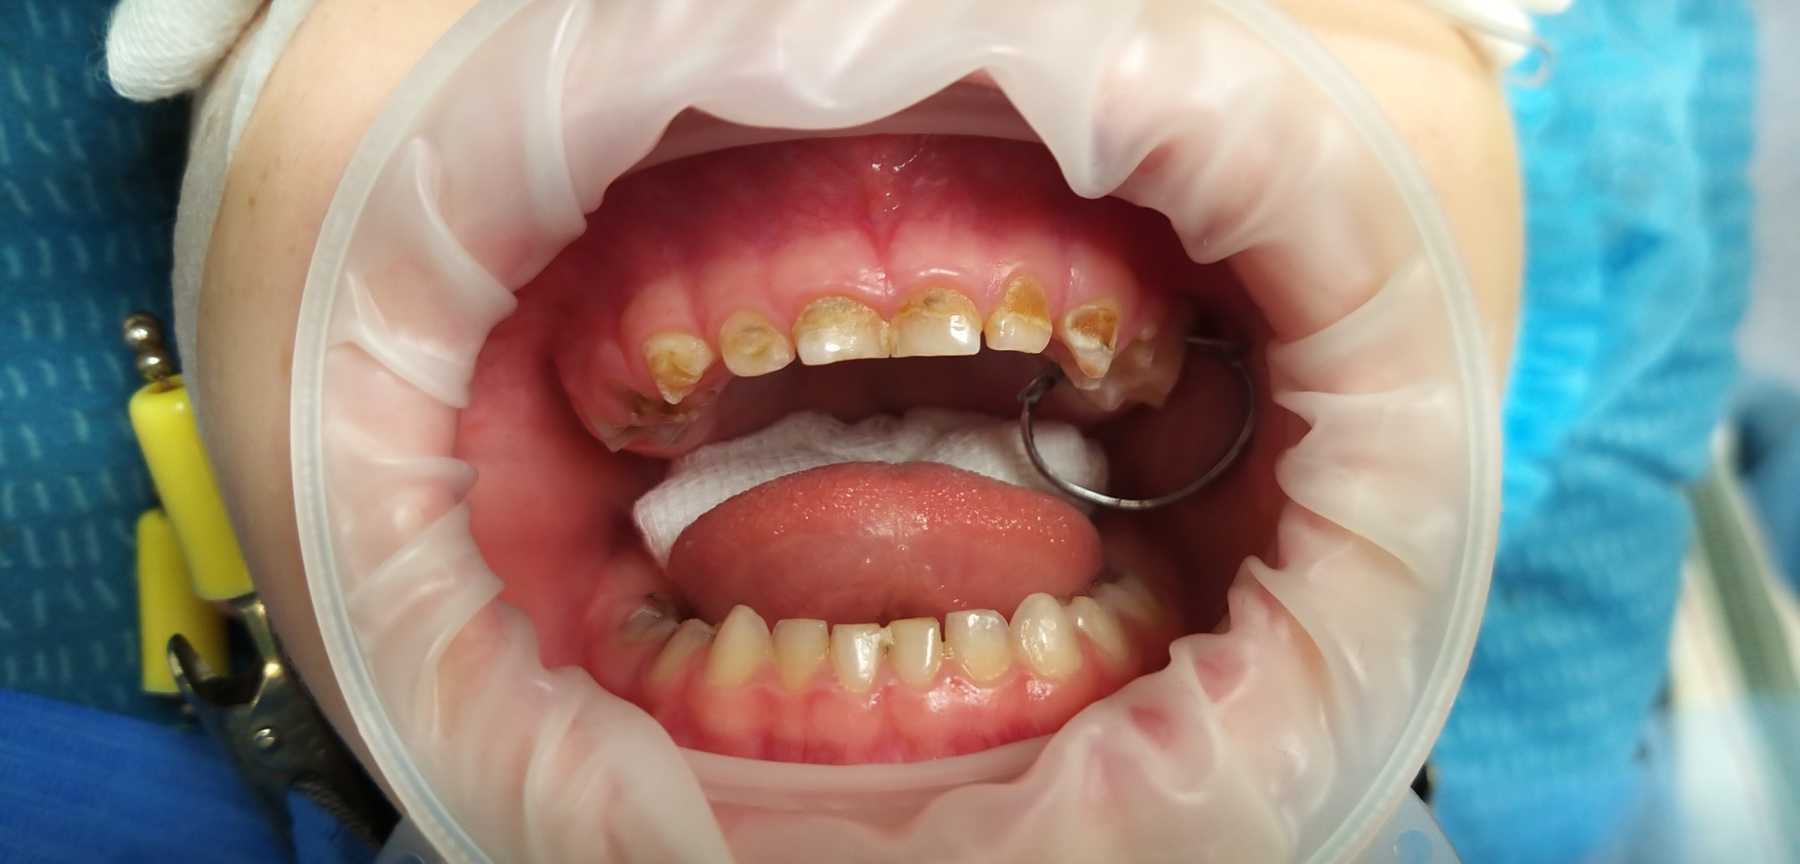

Стартувавши у 2009 році як одна з перших приватних клінік у Борисполі, «Здорова усмішка» і до сьогодні впевнено утримує позиції лідера на ринку стоматологічних послуг. Все це завдяки багаторічному досвіду, дотриманню чітких стандартів якості та постійному впровадженню інновацій. Свідченням цього є усмішки не лише киян, а й пацієнтів з багатьох країн світу.

Дружина Катерина Володимирівна

Лікар стоматолог - терапевт

Час не стоїть на місці, і ми впевнено крокуємо разом з ним. Щороку з’являються дієві методики та нові підходи, сучасні матеріали, які ми активно застосовуємо в процесі лікування. Аби забезпечити найвищий рівень послуг, ми постійно вдосконалюємось та навчаємось, беручи активну участь в різних галузевих виставках, семінарах та конференціях.

Ми працюємо тільки з найкращими матеріалами: Нанокомпозити Filtek виробництва США.